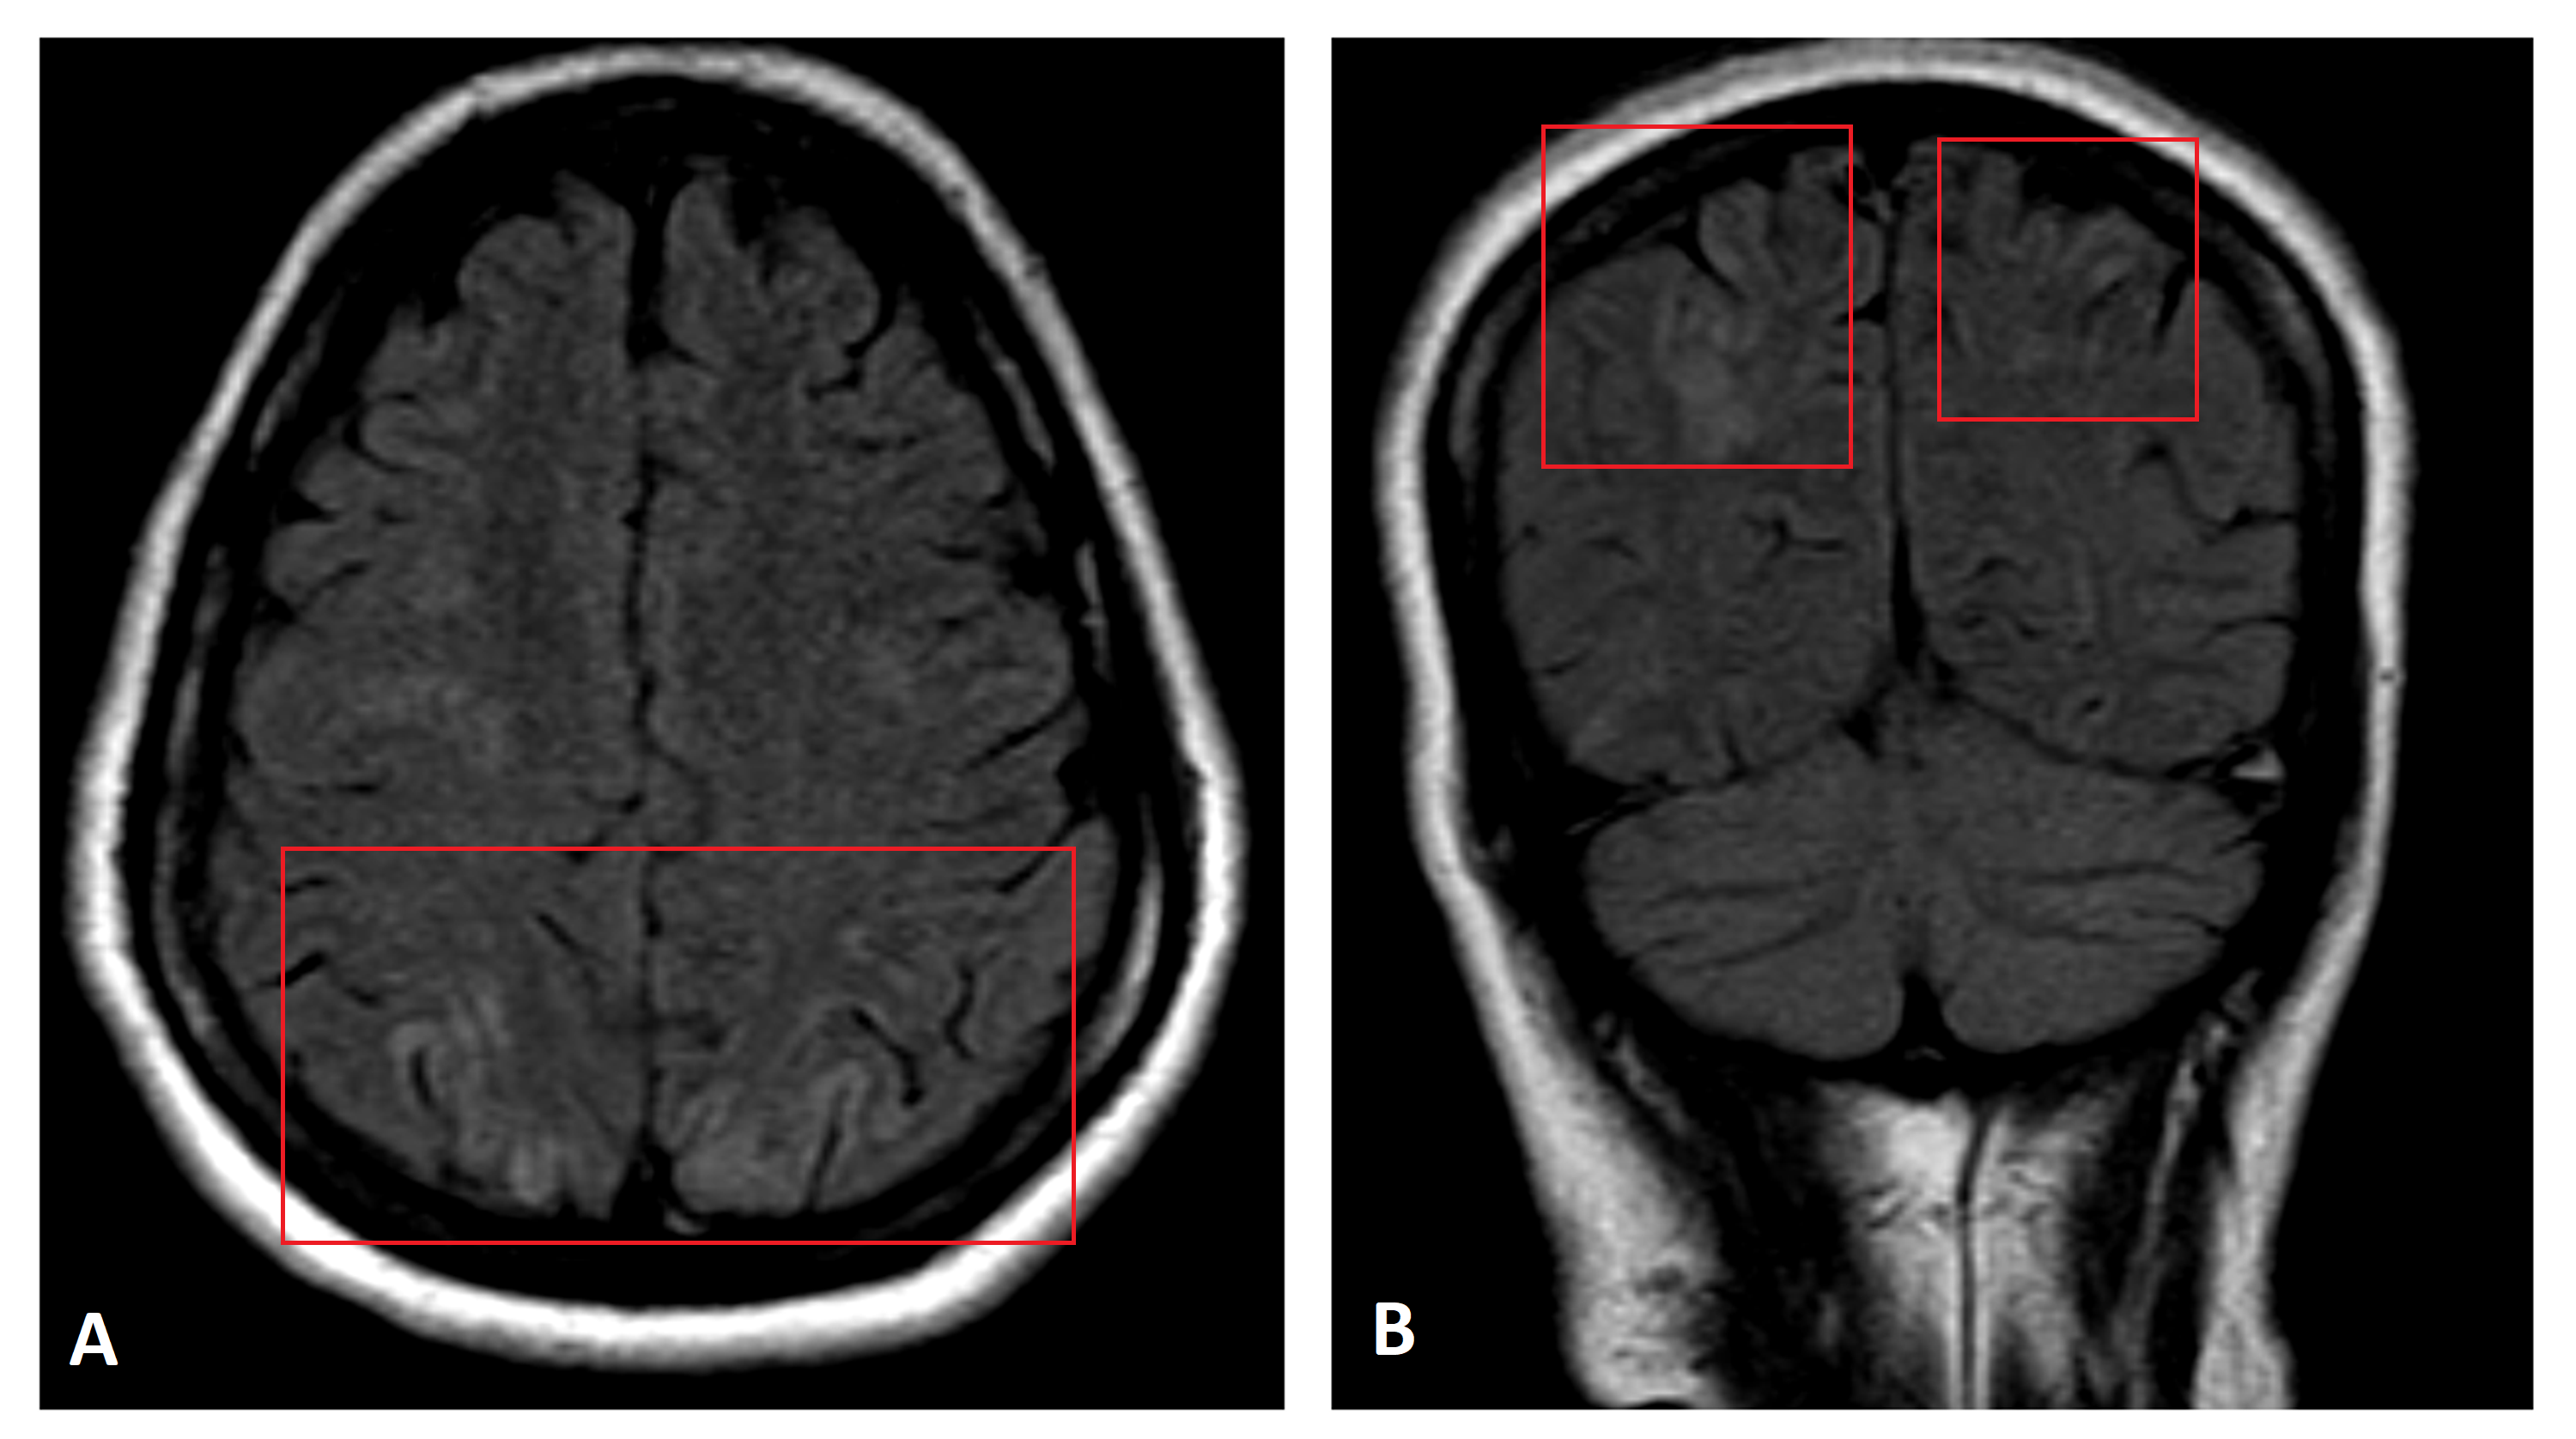

Figure 1 from Two Different Neuroimaging Patterns in Two Cases with Eclampsia Encephalopathy Recognized in the setting of a number of complex conditions (preeclampsia/eclampsia, allogeneic bone marrow transplantation, organ transplantation, autoimmune disease and high dose chemotherapy) the imaging. Posterior reversible encephalopathy syndrome (pres) is a neurotoxic state coupled with a unique ct or mr imaging appearance. Posterior reversible encephalopathy syndrome (pres) is a clinicoradiological diagnosis that is based on a combination of typical. Eclampsia Encephalopathy.